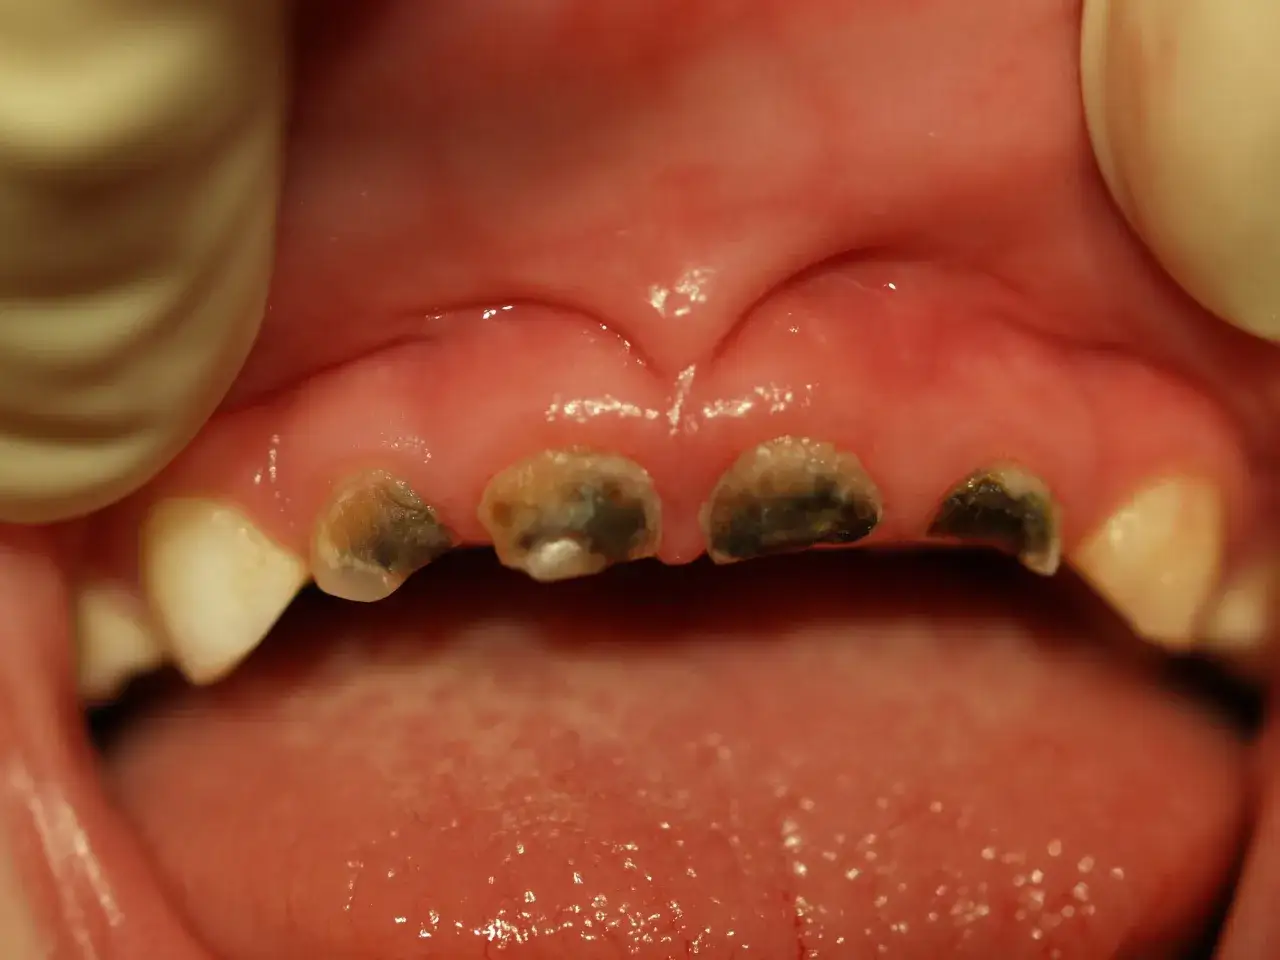

Próchnica jako najważniejsza i najczęstsza przyczyna ciemnych zmian

Próchnica jest niestety najczęstszą przyczyną ciemnych zmian na zębach u dzieci. Może ona objawiać się w różny sposób – od białych plam, które są wczesnym stadium demineralizacji szkliwa, przez brązowe, aż po czarne, widoczne ubytki. Jeśli zmiana wygląda jak dziurka, towarzyszy jej ból podczas jedzenia, picia, a zwłaszcza nadwrażliwość na zimno czy ciepło, to sygnały alarmowe. W takiej sytuacji konieczny jest szybki kontakt z dentystą, ponieważ próchnica postępuje szybko, zwłaszcza w zębach mlecznych, i może prowadzić do poważnych konsekwencji, takich jak infekcje i przedwczesna utrata zębów.Zewnętrzny czarny osad i przebarwienia przy linii dziąseł

Jak wyglądają ubytki próchnicowe i uszkodzone szkliwo

Ubytki próchnicowe wyglądają zupełnie inaczej. Mogą przybierać różne odcienie – od początkowych białych, matowych plam, przez brązowe, aż po głębokie, czarne dziurki. Próchnica to proces demineralizacji i zniszczenia struktury zęba. Zmieniona tkanka zęba może być miękka w dotyku (w zaawansowanej próchnicy), a często towarzyszy jej ból, nadwrażliwość na bodźce (zimno, ciepło, słodkie) lub widoczny ubytek, czyli dziurka. W przeciwieństwie do osadów, próchnicy nie da się zetrzeć, a jej postępujące zniszczenie zęba wymaga interwencji stomatologicznej.